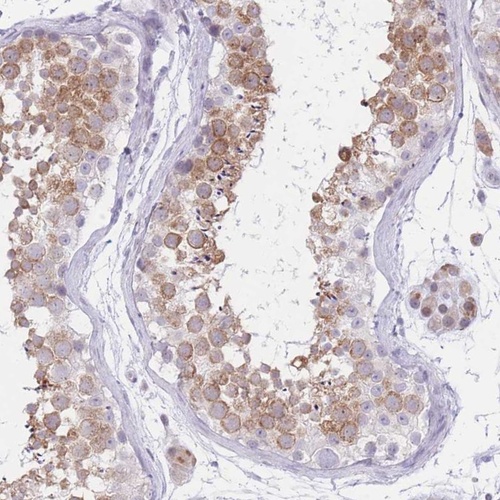

Immunohistochemical staining of human testis shows moderate cytoplasmic positivity in cells of seminiferous ducts.